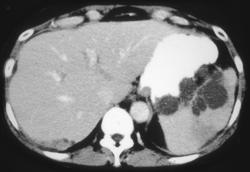

Splenic Infarction